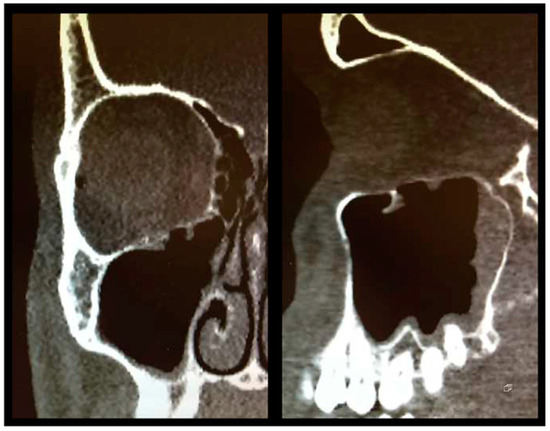

As described above, all patients underwent a first ophthalmologic examination on the day of admission. Following the decline of the frequently present periorbital swelling, all patients had a detailed orthoptic assessment preoperatively. The mean time elapsed from injury to the detailed orthoptic assessment was 1.93 days (SD = 1.45; range: 0–7 days). The mean time between the day of injury and the surgical repair using Ethisorb® patches was 4.33 days (SD = 2.71; range: 0–13 days). A representative example of a typical case is illustrated in Figure 2 and Figure 3 showing both the pre- and postoperative CT scans.

Figure 2.

Preoperative CT scan showing a large OFF ((left) coronal view, (right) sagittal view).